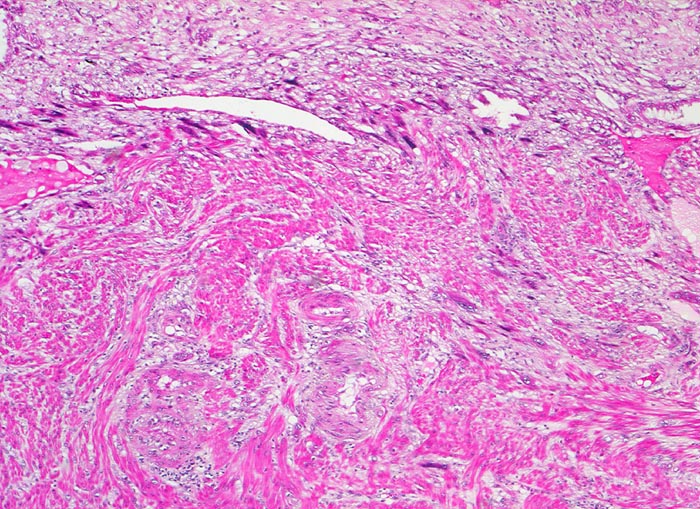

Beschreibung

Extravillöser Trophoblast invadiert das Myometrium. Die Trophoblastzellen sind grösser als die glatten Muskelzellen des Myometriums und haben grosse hyperchromatische Kerne. Oben im Bild Anschnitt der Dezidua.

11. Schwangerschaftswoche. Normale Schwangerschaft

Als extravillöser Trophoblast werden die Trophoblastzellen der Haftzotten, der Trophoblastinseln zwischen den Zotten, des Chorion laeve und der Spiralarterien bezeichnet. Der villöse Zytotrophoblast findet sich ausschliesslich in Verbindung mit einer Basalmembran. Je weiter die Zellen des extravillösen Trophoblasten (=Intermediärtrophoblast) von der Basalmembran entfernt sind, um so mehr verlieren sie ihr Wachstumspotential und differenzieren zu Zellen mit invasiven Eigenschaften.